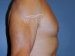

Male Nipple Reduction Patient 06

This 60 year old man is in excellent shape and condition. He has always been bothered by slightly protuberant nipples. He had the nipples reduced using local anesthesia in the office setting. His only wish was that he had done the procedure years ago.

Months Post Op: 4